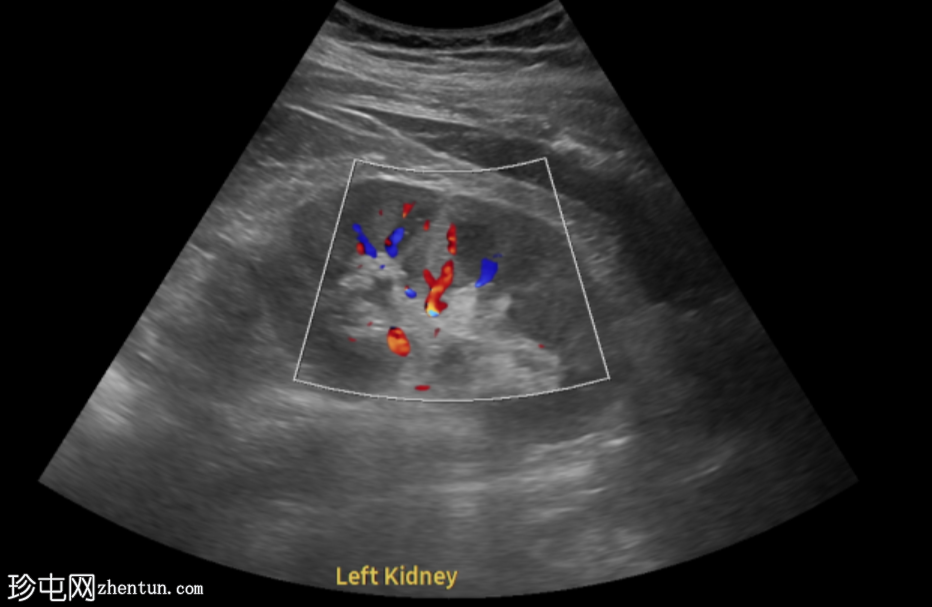

超声显示左侧轻度肾积水,由膀胱输尿管连接处一枚7毫米的远端输尿管结石阻塞所致,输尿管射流正常。

肾积水并非总是由输尿管结石引起。肾盂和肾盏扩张的程度与结石大小并不一定相关。

较小的结石有时可导致中度上游扩张,而较大的结石可能仅引起轻微的充盈感,这取决于患者的引流和水合状态。